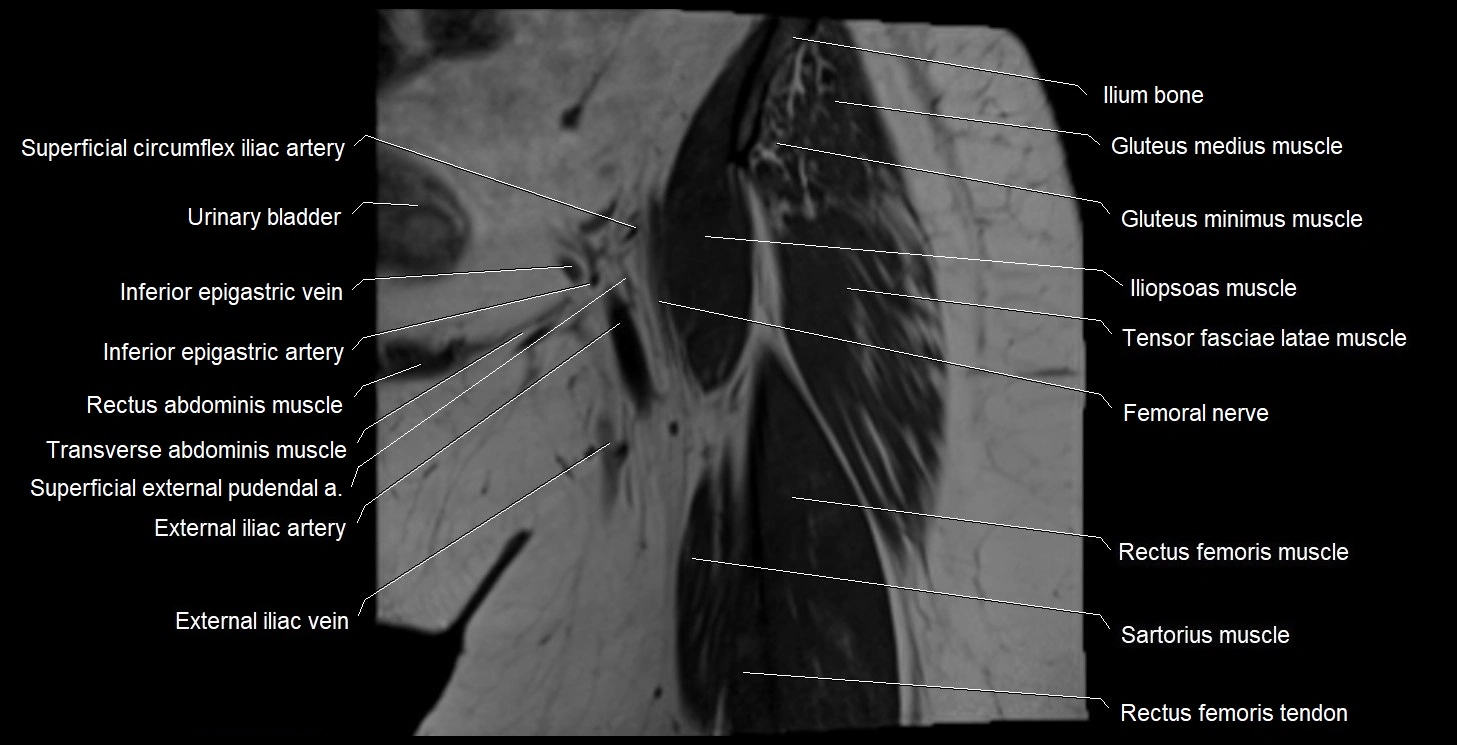

- External iliac artery

- External iliac vein

- Femoral nerve

- Gluteus medius muscle

- Gluteus minimus muscle

- Iliopsoas muscle

- Inferior epigastric artery

- Inferior epigastric veins

- Rectus femoris muscle

- Rectus femoris tendon (Proximal tendon of rectus femoris)

- Sartorius muscle

- Tensor fasciae latae muscle

- Urinary bladder